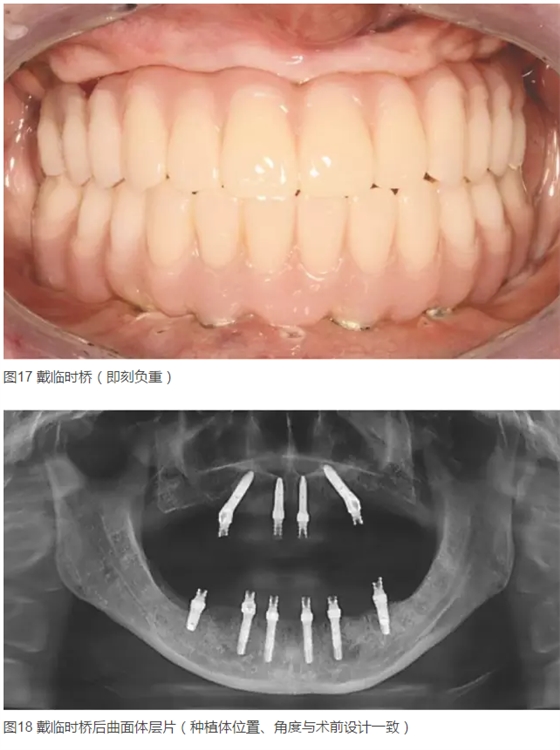

患者女,42歲。1年前因牙周病拔除全口牙齒,行全口活動(dòng)義齒修復(fù),現(xiàn)自覺(jué)影響咀嚼和生活來(lái)診。要求:牙種植修復(fù)后即刻可使用。